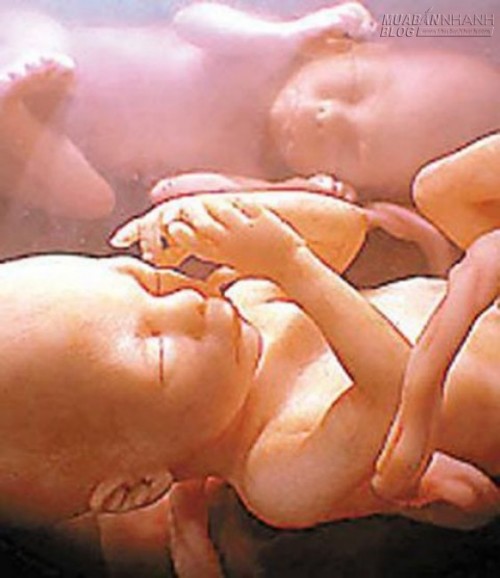

Nói về sự tương tác của các cặp song sinh từ khi còn ở trong bụng mẹ, trong một nghiên cứu khác, các bác sĩ Anh là những người đầu tiên công bố trên phương tiện thông tin đại chúng chùm ảnh đa thai, đem đến nhiều bất ngờ cho người xem. Bộ ảnh ghi lại chi tiết cuộc sống của các cặp sinh đôi và sinh ba, từ khi thụ thai đến lúc sắp chào đời. Không như suy nghĩ của nhiều người, các em bé đã bắt đầu phát tín hiệu tương tác với nhau từ khá sớm. Thông qua những hình ảnh ghi được như cái nắm tay, tư thế đối mặt hay đối đầu, thơm má và xô đẩy nhau... đã cho thấy sự phát triển cả về thể chất lẫn tinh thần của mỗi thai nhi. Các chuyên gia cũng cho rằng những hành động này có thể ảnh hưởng đến cách đứa trẻ biểu lộ cảm xúc sau này.

Một số hình ảnh ngộ nghĩnh khác về sự tương tác của các cặp song sinh trong bụng mẹ.

Một em bé giơ tay che mắt khi bị chói và em bé khác đang làm hành động như thể bị tiếng ồn bên ngoài làm cho khó chịu.

Khi thai còn nhỏ, các bé có thể thoải mái xoay đầu, di chuyển trong bụng mẹ. Mỗi em bé chọn một tư thế nằm thích hợp.